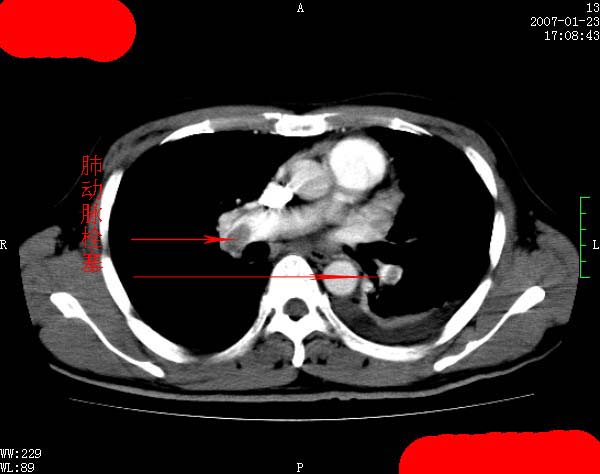

以下是引用jiangjing在2007-1-24 23:35:00的发言:[br]支持 增强扫描见右肺动脉干、左下肺动脉见充盈缺损。印象为:1、右肺动脉干、左下肺动脉栓塞。 2、左侧胸腔积液合并左肺下叶被动性肺不张。

以下是引用rjg199343在2007-1-24 23:22:00的发言:[br]增强扫描见右肺动脉干、左下肺动脉见充盈缺损。印象为:1、右肺动脉干、左下肺动脉栓塞。 2、左侧胸腔积液合并左肺下叶被动性肺不张。

以下是引用影象王在2007-1-25 10:16:00的发言:[br]肺栓塞。确实典型!